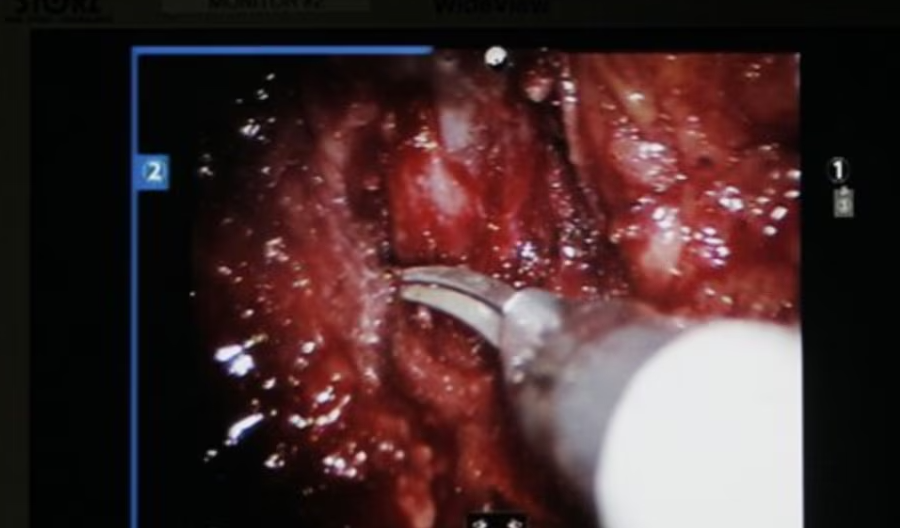

Por, krahë robotikë kryejnë një operacion delikat në rrugët urinare të pacientit.

Krahët robotikë bëjnë pjesën më të madhe të punës, ndërsa kirurgu kryesor përdor leva për t’i kontrolluar dhe drejtuar ato.

Ndërsa krahët robotikë të përdorur në këtë procedurë kanë një gamë lëvizjeje të tillë që bën të mundur që instrumente kirurgjikale mjaft të vogla të kryejnë operacione të ndërlikuara te fëmijët.

Pajisja e ndihmuar nga roboti, e zhvilluar nga CMR Surgical Ltd me bazë në Kembrixh, synon të arrijë një saktësi që njeriu nuk e arrin dot, nëpërmjet përdorimit të instrumenteve të vogla kirurgjikale, kontrollit të robotit, si dhe një ekrani të zmadhuar me rezolucion të lartë.

“Ndërhyrja kontrollohet nga kirurgu, gjithsesi. Duket sikur ndihma robotike është e atomatizuar, por në fakt kontrollohet nga kirurgu”, thotë kirurgu Ewan Brownlee